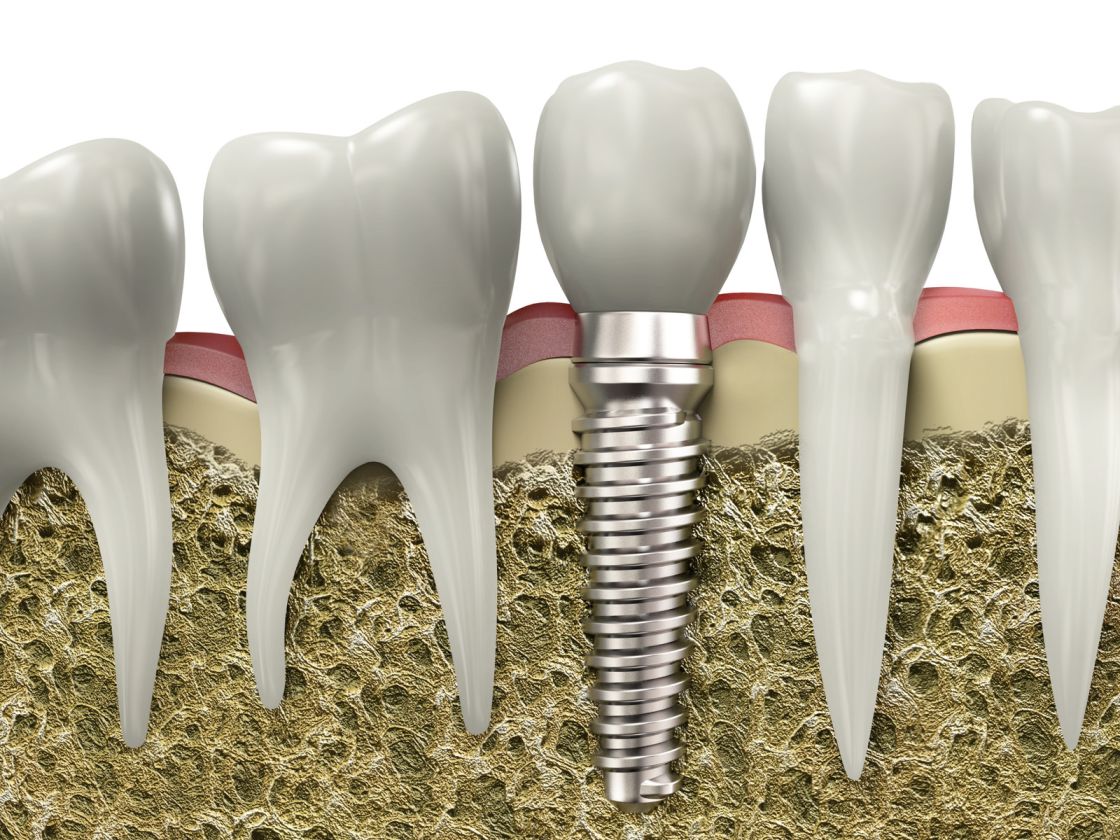

کلینیک دندانپزشکی وارستگان با رویکردی نوین در ارائه خدمات دندانپزشکی، محیطی حرفهای و در عین حال صمیمی برای مراجعان فراهم کرده است. در این مرکز خدمات متنوعی از جمله درمانهای ترمیمی، زیبایی دندان، ارتودنسی، ایمپلنت و درمانهای کودکان ارائه میشود.